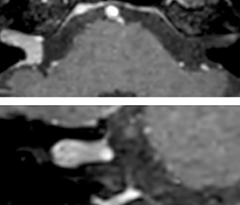

Giant cell arteritis

The 3D TSE T1w black blood MSDE sequence with fat suppression has an isotropic 0.8 mm voxel size and sagittal oblique and axial reformats are made. The images show superficial temporal artery thickening and peri-arterial fat infiltration. The 3D TSE PDw black blood MSDE with fat suppression has 0.55 mm isotropic voxels. The images shows focal involvement of the frontal branch of the superficial temporal artery.

3D TSE T1w BB MSDE

3D TSE PDw BB MSDE

So, what is the actual impact of having more information and more diagnostic confidence? According to Dr. Savatovsky, “One of the indications I’ve seen where using Elition is most impactful is in patients with suspected giant cell arteritis. As an ophthalmologic hospital, we see many patients with suspected giant cell arteritis. Usually we were performing MRI to help us rule out an ischemic stroke, and to verify that the supra aortic vessels are undamaged. With Elition, we still do this, but now we can add on more detailed high-resolution black-blood sequences on superficial arteries. This provides us with high confidence levels for diagnosis of giant cell arteritis (GCA) and as a result, some patients are not sent for a biopsy anymore. A patient who has a normal MRI will not require a biopsy and can be discharged from the hospital in the same day. Before, such a patient would have to stay for about a week, just to find that their biopsy results were negative. We have at least three or four patients a week with suspected giant cell arteritis. For a great deal of these patients we can have a direct impact on their hospital stay.”